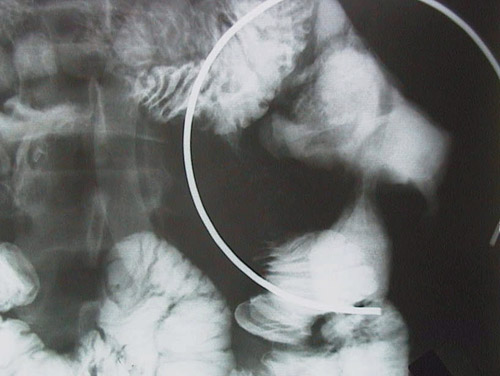

This upper GI series reveals a focal area of stricture in the terminal ileum, consistent with Crohn's disease, which is a form of idiopathic inflammatory bowel disease that typically has remissions and exacerbations over many years.